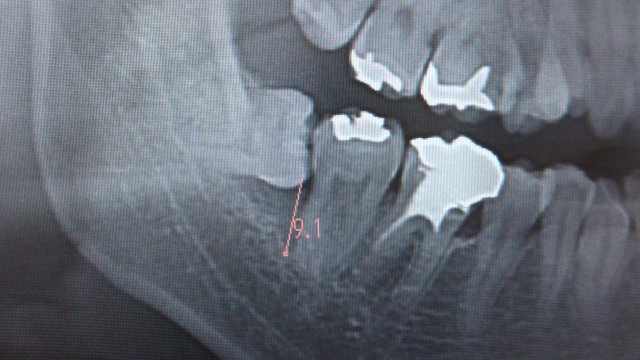

7.1ミリ骨が溶けました。

5.3ミリ骨が溶けました。虫歯にもなっていそうです。

7.9ミリ骨が溶けました。

26.5-15.7=約11ミリ骨が溶けました。

9.1ミリです。